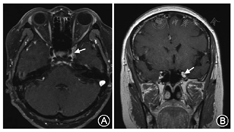

51例炎症性疾病中,疼痛发生比例较其他组显著增高,差异有统计学意义(χ2=9.743,P=0.002);动眼神经受累更常见[42例(82.3%)],与其他组比较差异有统计学意义(χ2=6.559,P=0.012,表3)。THS中42例(87.5%)为单侧海绵窦受累,单颅神经受累者21例(43.6%),2条颅神经受累13例(27.1%),3条及以上颅神经受累者14例(29.2%)。THS中复发病程者9例(18.7%),其中4例复发次数2次以上,1例20年内复发10次(图1)。THS中病变累及脑膜者9例,累及眶尖10例,累及眶上裂3例。THS中伴自身免疫指标异常者3例。THS中接受腰穿检查者36例,其中有异常者4例(11.1%)。THS中43例接受激素治疗,随访时均有好转。本组THS中1例最初诊断为海绵窦结核瘤并抗结核治疗,3年后因视力下降接受手术治疗,病理诊断为非特异性炎症;3例因影像学考虑肿瘤可能性大而行手术治疗,病理诊断为非特异炎症。

肿瘤是本组海绵窦区病变第二位病因,其中以脑膜瘤最常见。本组患者三叉神经第二支受累多见,与其他组比较差异有统计学意义(χ2=5.213,P=0.022,表3)。本组肿瘤患者中,有4例(9.3%)早期诊断为THS接受激素或其他免疫治疗,随访时确诊为肿瘤性疾病,包括淋巴瘤1例,腺性囊样癌1例,乳腺癌转移1例,肺癌转移1例。本组1例海绵窦原发性组织细胞肉瘤,为国内首例报道。患者女性,51岁,亚急性起病,头痛复视1个月,MRI示右海绵窦病变(图2),曾在外院诊为THS而接受激素治疗。手术病理证实为组织细胞肉瘤(图3,图4),术后半年死亡。